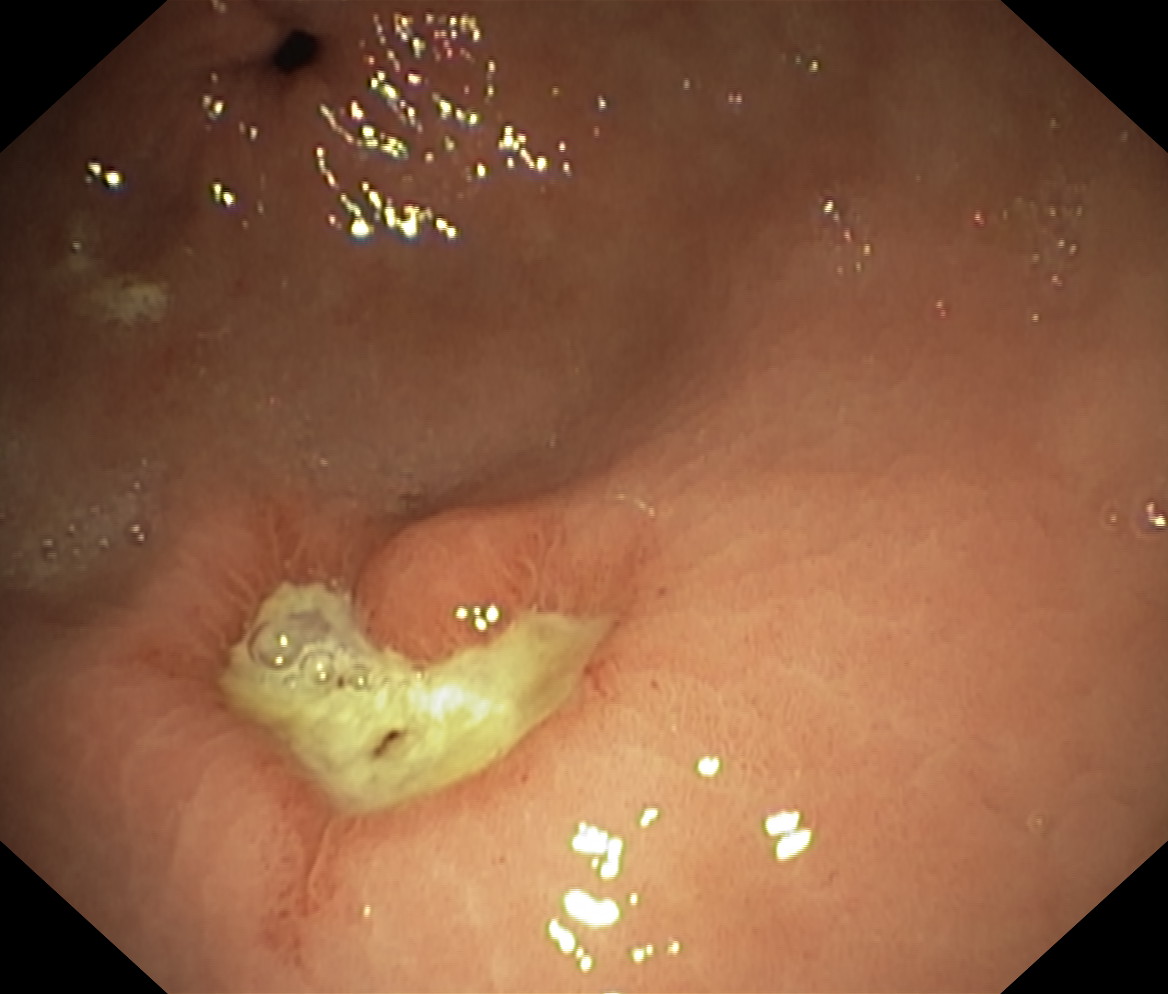

Wrzód trawienny